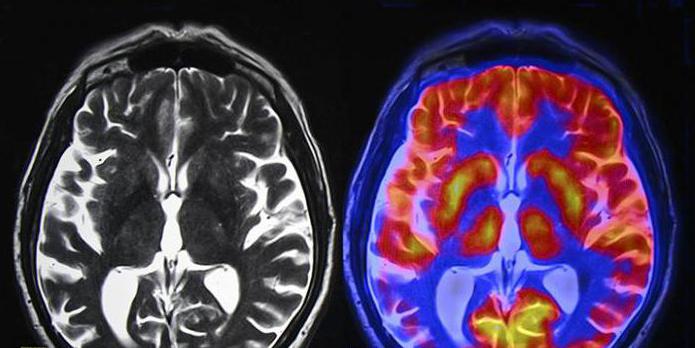

ЦНС – это главный регулятор работы всего организма. Ведь в корковых структурах мозга имеются отделы, отвечающие за функционирование каждой системы. Благодаря ЦНС обеспечивается нормальная работа всех внутренних органов, регуляция выделения гормонов, психоэмоциональное равновесие. Под воздействием неблагоприятных факторов происходят органические повреждения структуры головного мозга. Зачастую патологии развиваются на первом году жизни ребенка, но могут диагностироваться и у взрослого населения. Невзирая на то, что ЦНС непосредственно связана с органами благодаря нервным отросткам (аксонам), поражение коры опасно из-за развития тяжёлых последствий даже при нормальном состоянии всех функциональных систем. К лечению заболеваний головного мозга нужно приступить как можно раньше, в большинстве случаев оно проводится длительно — на протяжении нескольких месяцев или лет.

Как известно, ЦНС представляет собой слаженную систему, в которой каждое из звеньев выполняет важную функцию. Вследствие чего поражение даже малого участка мозга может привести к нарушению в работе организма. В последние годы повреждение нервной ткани всё чаще наблюдается у пациентов детского возраста. В большей степени это касается только родившихся малышей. В подобных ситуациях выставляется диагноз «резидуально-органическое поражение ЦНС у детей». Что это такое и поддаётся ли данное заболевание лечению? Ответы на данные вопросы беспокоят каждого родителя. Стоит иметь в виду, что подобный диагноз представляет собой собирательное понятие, в которое может входить множество различных патологий. Подбор терапевтических мероприятий и их эффективность зависят от распространённости повреждения и общего состояния пациента. Иногда резидуально-органическое поражение ЦНС встречается у взрослых. Зачастую патология возникает вследствие перенесенных травм, воспалительных заболеваний, интоксикации. Понятие «резидуально-органическое поражение ЦНС» подразумевает какие-либо остаточные явления после повреждения нервных структур. Прогноз, а также последствия при подобной патологии зависят от того, насколько сильно нарушена функция головного мозга. Помимо этого, огромное значение придается топическому диагнозу и выявлению места повреждения. Ведь каждая из структур мозга должна выполнять определенные функции.

Резидуальное поражение ЦНС всегда вызвано неблагоприятными факторами, предшествовавшими ранее. В большинстве случаев основой патогенеза подобных симптомов является ишемия головного мозга. У детей она развивается ещё в период внутриутробного развития. Из-за недостаточного кровоснабжения плаценты плод получает мало кислорода. В результате нарушается полноценное развитие нервной ткани, возникают фетопатии. Значительная ишемия приводит к задержке внутриутробного развития, рождению ребёнка раньше срока гестации. Симптомы гипоксии головного мозга могут проявляться уже в первые дни и месяцы жизни. Резидуально-органическое поражение ЦНС у взрослых чаще развивается вследствие травматических и инфекционных причин. Иногда патогенез нервных расстройств связан с метаболическими (гормональными) нарушениями.